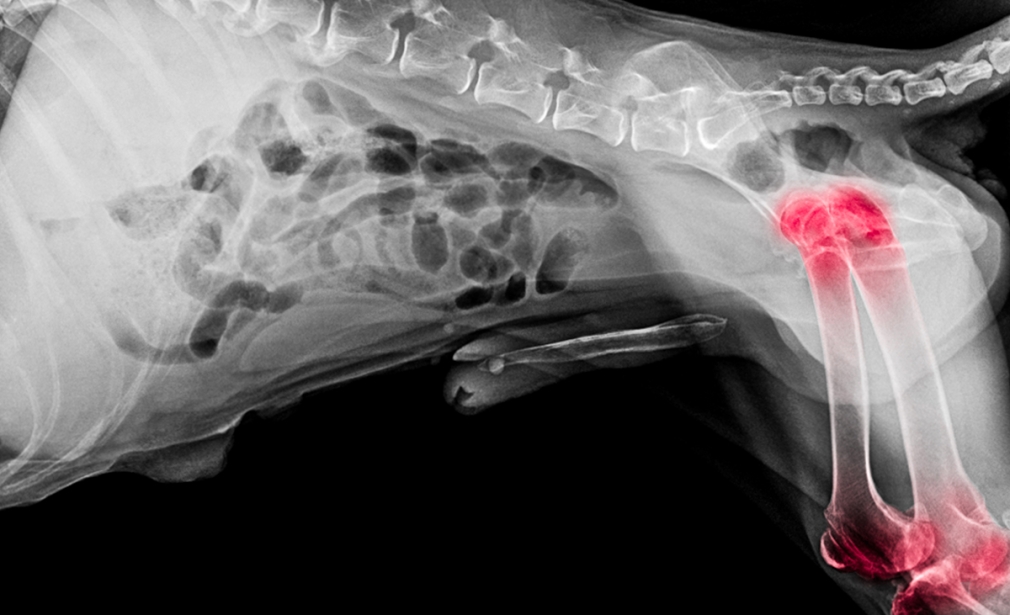

Our orthopaedic service specializes in the surgical treatment of musculoskeletal issues, offering relief and enhanced mobility for pets suffering from conditions like fractures, joint dysplasia, and ligament tears. We utilize the latest techniques to ensure the best outcomes for your pet’s recovery and mobility.

A comprehensive evaluation including x-rays and ultrasound to determine the exact nature of your pet’s condition.